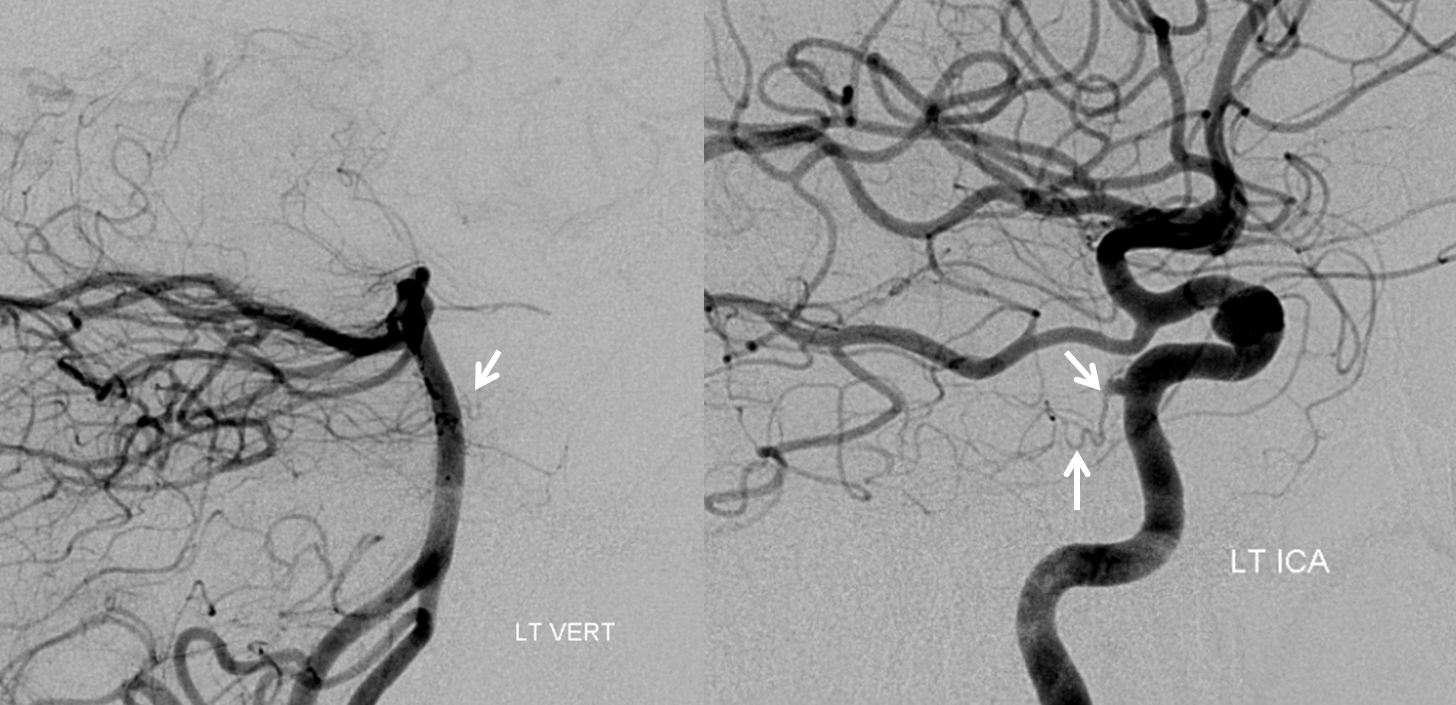

Trigeminal Artery and PCOM fenestration — not only does this person have a PCOM, but a fenestrated one — a finding that is exceedingly rare — I’ve only seen one. There is one report of it in the literature, however this report does not seem to have images. So, this one is the only fenestrated PCOM image in the world I know of — except for all the ones being hidden somewhere for no useful purpose. Therefore, if you have any, please SHARE — like they told you in childhood. Credits guaranteed. Stereoscopic image below courtesy of Dr. Nelson and Dr. Becske

Anaglyph